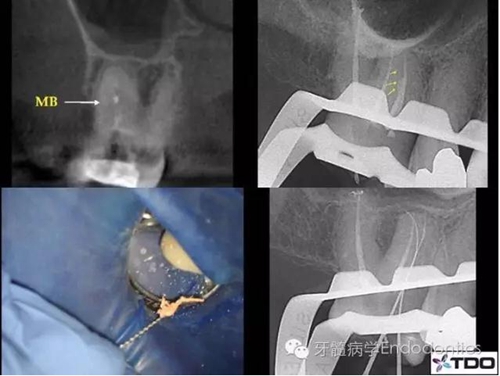

二診充填根管后的X線片可看到MB根管上段粗大,下段突然變窄,糊劑進(jìn)入了可能存在的MB2(根尖二分叉)中(圖2)。

三診時(shí),醫(yī)生從MB根管中取出牙膠尖,使用預(yù)彎的手銼疏通MB2并進(jìn)行清理、成形,牙膠+糊劑充填根管(圖3)。

圖2

圖3